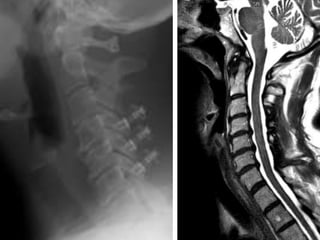

47 year old woman with 6 month h/o neck stiffness and pain with

left UE paresthesias into

The elbow forearm and hand especially IF/thumb

47 year oldwoman with 6 month h/o neck stiffness and pain with left UE paresthesias into The elbow forearm and hand especially IF/thumb

Mid-sagittal diameter: width

1:5 ratio leads to necrosis of gray

matter

Mid-sagittal diameter: width 1:5ratio leads to necrosis of gray matter • Ogino H: Canal diameter, anteroposterior compression ratio and spondylotic myelopathy of the cervical spine. Spine 1983; 8:1-15 • Cord compression causes ischemia and direct mechanical trauma